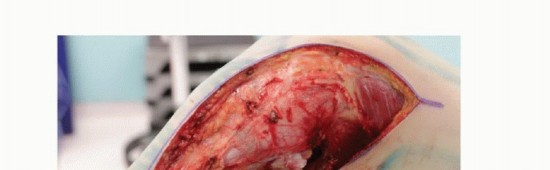

* قلة التغطية العضلية: الجزء الأمامي الإنسي من قصبة الساق يتميز بقلة الأنسجة الرخوة التي تغطيه، مما يزيد من خطر انكشاف الغرسات أو الطعوم العظمية وحدوث العدوى.

تتطلب هذه التحديات خبرة جراحية فائقة ودقة متناهية، وهو ما يتوفر في عيادة الأستاذ الدكتور محمد هطيف، الذي يمتلك المعرفة والمهارة للتعامل مع هذه الحالات المعقدة بنجاح، مستخدماً أحدث التقنيات لضمان أفضل النتائج.